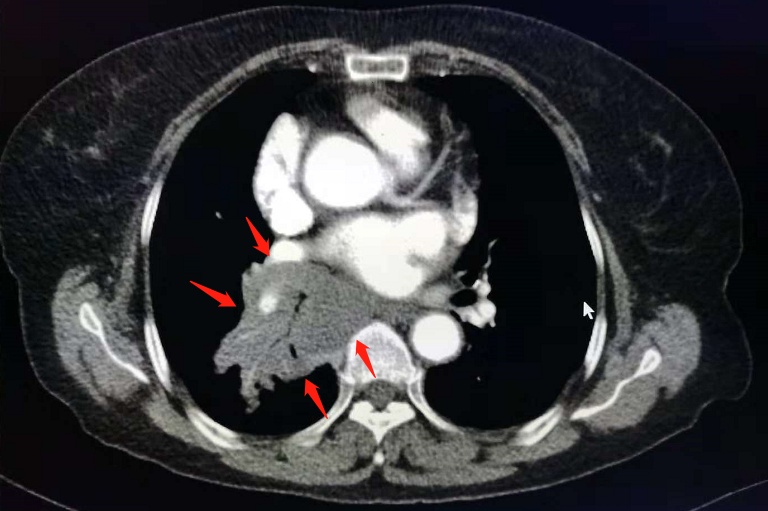

像这位病人,反复胸闷两个月,小细胞肺癌并广泛转移。

化疗两个周期后复查,病灶显著缩小: